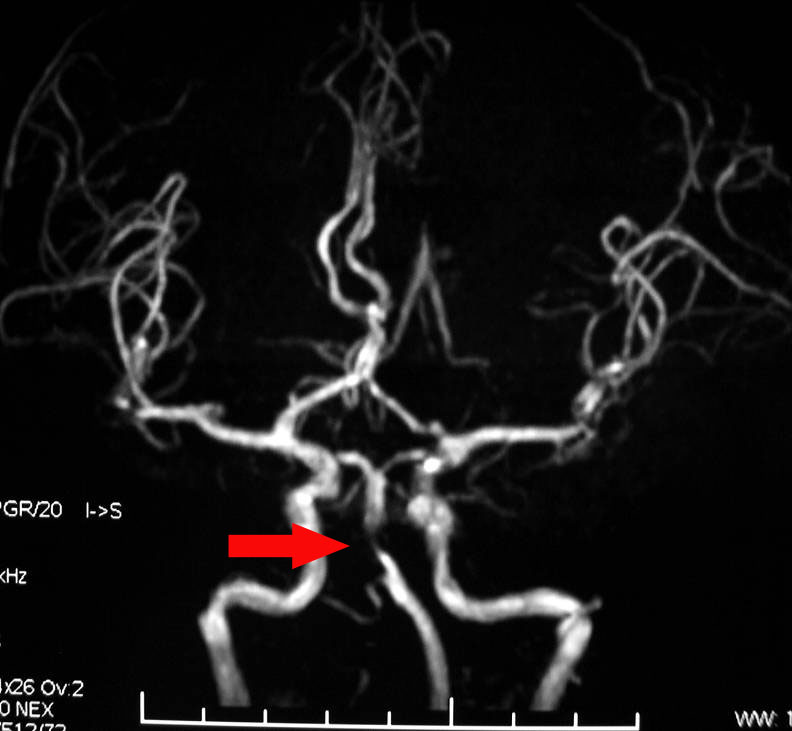

腦血管狹窄是造成缺血性腦血管病的一個(gè)重要病因和危險(xiǎn)因素。腦血管狹窄使得經(jīng)過(guò)腦血管的血液減少,腦細(xì)胞就會(huì)缺血死亡。 專家表示造成腦血管狹窄的原因很多,而且與年齡有關(guān),如結(jié)節(jié)性動(dòng)脈炎引起的血管狹窄發(fā)病年齡多在10~30歲,而由于動(dòng)脈硬化狹窄者往往為40~80歲的中老年人,甚至更高年齡者。兒童發(fā)病者,多由于先天性的血管發(fā)育異常造成,頸椎病也是腦血管狹窄的誘發(fā)因素。

腦血管狹窄的癥狀主要有頭昏、眩暈、惡心、嘔吐,腦血管狹窄是各種原因引起的腦血管變細(xì)。甚至造成意識(shí)不清等,容易被誤診為“美尼爾氏綜合癥”此病多由高血壓、高血脂、高血糖等原因引起,也有血管炎癥、腫瘤等原因引起。因此一定要及時(shí)的發(fā)現(xiàn)和治療。